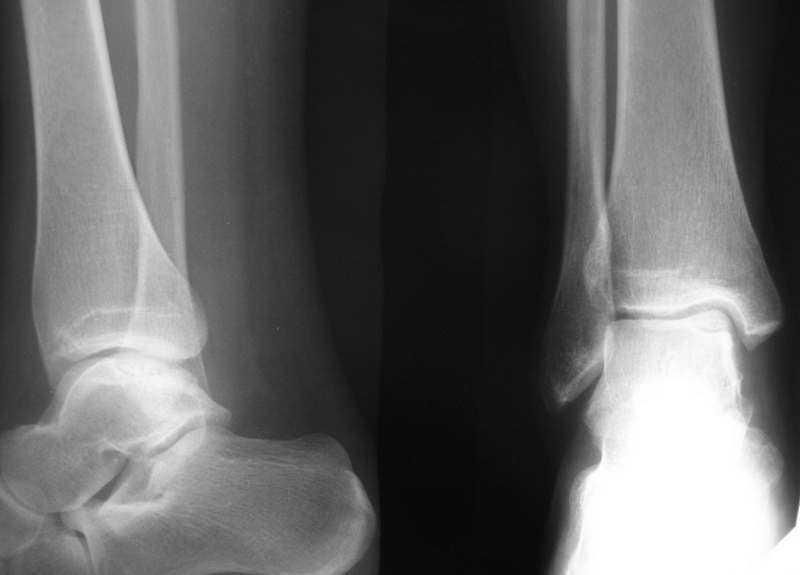

Больная М., 30 лет, около полугода беспокоят боли в голеностопном суставе. На рентгенограммах и КТ признаки остеохондропатии блока таранной кости.(РКТ на бумаге поэтому не выкладываю) Выносится на обсуждение тактика: 1. Просто ждать, назначив разгрузку сустава, физиолечение, ЛФК. 2. Артротомия сустава, фиксация винтом типа Герберта. 3. Артроскопия или артротомии с удалением фрагмента.